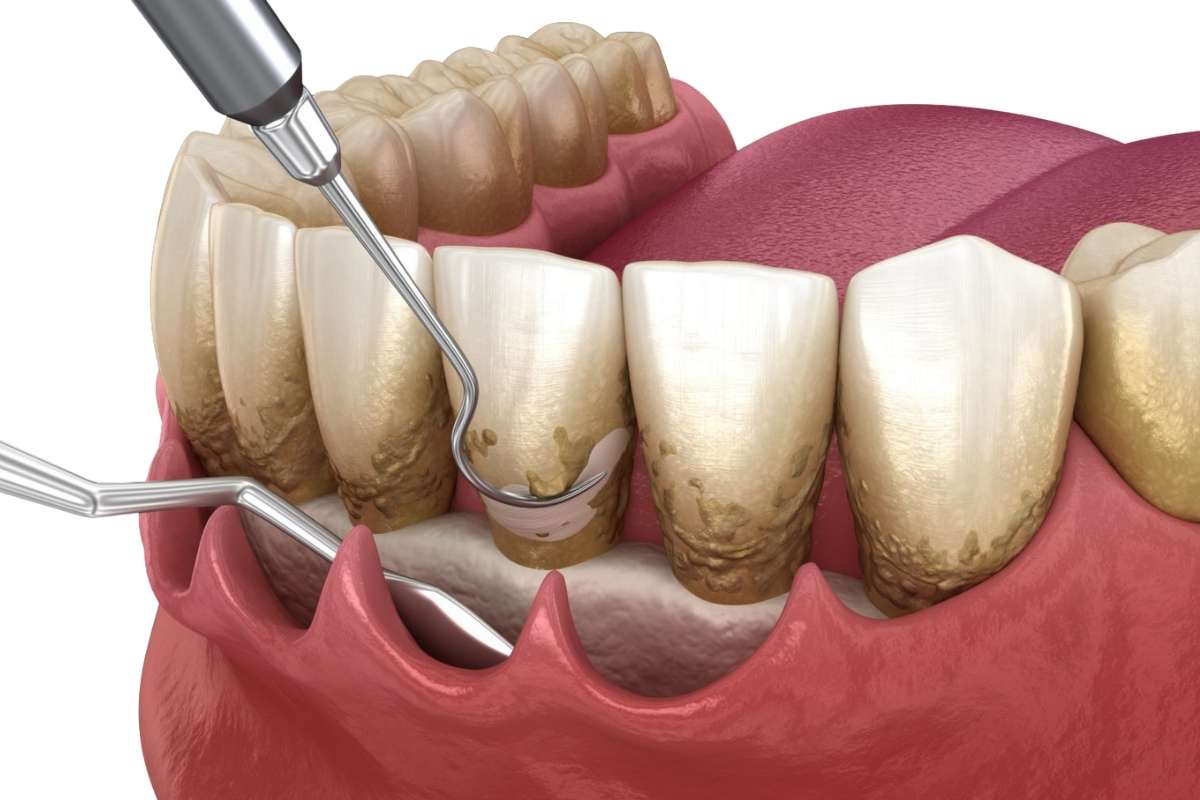

Why You Still Get Plaque Even After Brushing and Flossing

You brush twice a day, floss regularly, and still notice…